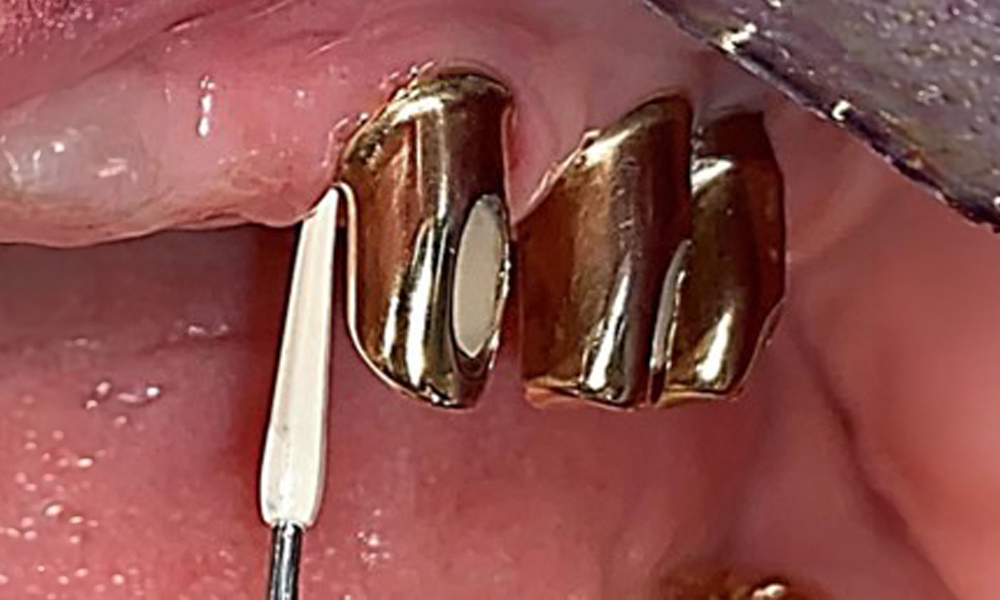

Occlusal view: Maxilla with tooth and implant-supported telescopic prostheses.

Fig. 2: Occlusal view: Maxilla with tooth and implant-supported telescopic prostheses

The dental findings are as follows: Combined removable implant and tooth-supported telescopic prostheses on implants 15, 13, 21, 23, 24, 25 and tooth 11 (Fig. 1, Fig. 2, Fig. 3). The patient was fitted with a fixed mandibular denture. Adequate bridges were present over 37 to 34 and 45 to 47 (Fig. 4), the crown margins were intact and there were no active caries. A composite filling with a marginal gap was present on tooth 43. There was mandibular gingival recession, exposing 1 to 3 mm of root surface. This also applies to 11.

The patient was fitted with a combined removable maxillary telescopic prosthesis more than 25 years ago (Fig. 1, Fig. 2, Fig. 3) and is very happy with her dentures. The patient has an adequate fixed denture for the mandible (Fig. 4).